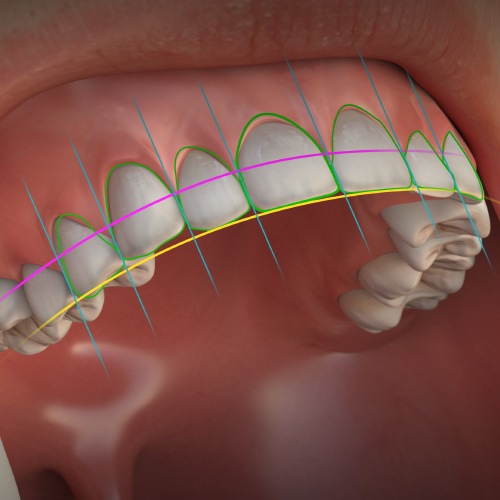

Esthetic Dentistry Updates

Thursday, August 15, 2024

This Compendium eBook features a continuing education (CE) article on the benefits of digital smile design for digitally strategizing treatments. This eBook also includes a case report article demonstrating a workflow for bonded partial ceramic restorations that was used in a patient with a...